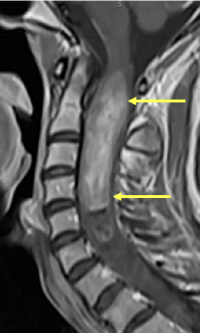

“That's when they said the mass was likely a very, very large intramedullary tumor,” she says. Spanning from the C1-C6 vertebrae, the tumor was thought to be benign, but its location inside the spinal cord was blocking the cerebrospinal fluid, which cushions and nourishes the brain and spinal cord. The tumor may have been growing slowly for 10-20 years. “It was a complete shock to me. But all the headaches and back pain started to make sense. Being in my profession, I knew how rare this was, and I was scared by how large it was.”

“The spinal cord is very delicate and only gentle surgical techniques can be applied in order not to injure it,” Dr. McCormick explains. “The location of Dr. Labib’s tumor was also a challenge because it was in an area of the spinal cord that not only controls sensation and movement in the arms and legs but also the ability to breathe.” An additional challenge was the tumor’s large size, extending from the top of the spinal cord at the first cervical level down to the fifth cervical level. But after many hours under the operating microscope, Dr. McCormick was able to remove the whole mass: “We took it out completely and cured her of the tumor.”